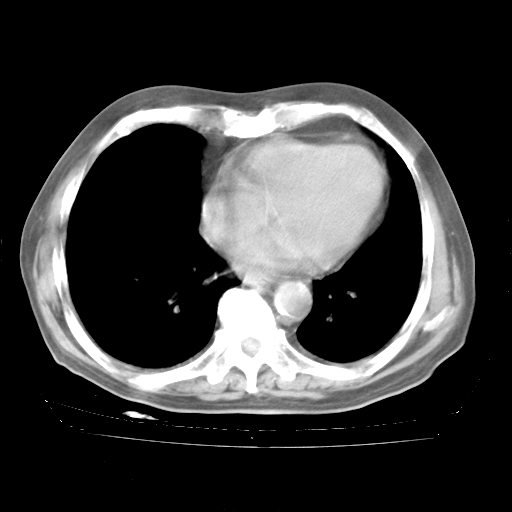

4月28日肺部CT——再次出现类似去年5月9日——透光度降低,“间质性”改变。

4月28日肺部CT——再次出现类似去年5月9日——磨玻璃样、间有“粟粒样”改变。